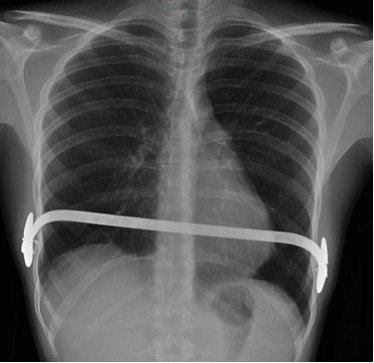

PECTUS EXCAVATUM.

Con una frecuencia de 8 por 1.000 recién nacidos vivos, constituye la más común de las deformidades congénitas de la pared anterior del tórax. Suele estar presente al nacer o comienza a evidenciarse durante el primer año de vida, acentuándose en la adolescencia. Predomina en varones 3:1 y pueden existir antecedentes familiares.

Es una depresión esternal interna, formando una concavidad, consecuencia de una anormalidad en el crecimiento del esternón y de los cartílagos costales. Suele ser asimétrica, de predominio derecho. Su etiología es desconocida aunque puede influir la tracción del diafragma.

Puede estar asociado escoliosis, Marfan, cardiopatía congénita, displasia broncopulmonar, enfermedades metabólicas o del tejido conectivo.

Suele ser asintomáticos. En casos de deformidades acentuadas, pueden causar dificultad respiratoria. La presencia de sintomatología debería hacer plantear un protocolo de estudio rápido.

El diagnóstico es clínico. Con la imagen evaluamos mejor la deformidad, útil en caso de ser necesaria la cirugía.

En la Rx de tórax se observa el borramiento del borde cardiaco derecho y en la placa lateral, la depresión interna del esternón, característicamente del cuerpo esternal y de la apófisis xifoides. En casos más acentuados, el corazón, los pulmones, el esófago y el diafragma pueden estar comprimidos, con desplazamiento del corazón hacia la izquierda y prominencia del tronco de la arteria pulmonar en la proyección PA; hallazgos mas evidentes gracias al TC y las reconstrucciones.

El tratamiento puede ser conservador o eventualmente quirúrgico.

Índice de Haller:

- Medio: 3,2

- Moderado: 3,2-3,5

- Severo: > 3,5 (cirugía).